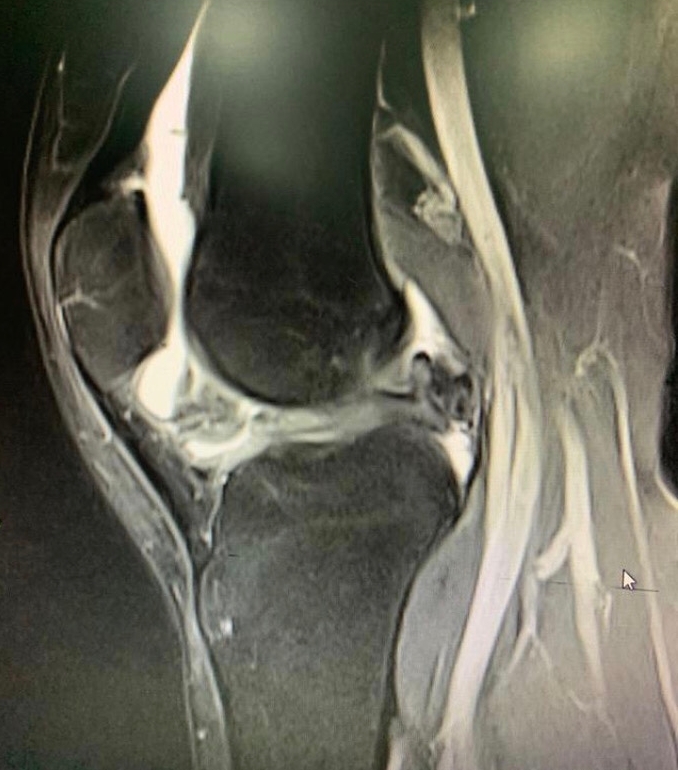

核磁共振显示的半月板损伤